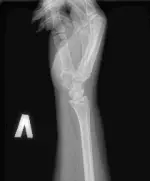

Рентгенографія променевозап’ясткового суглоба може проводиться в передньо-задній і бічній проекціях, з обов’язковою оцінкою стану кісток зап’ястя (ладьєвидної, півмісяцевої, тригранної).

З патології променевозап’ясткового суглоба найчастіше буває травма – перелом променевої кістки в «типовому» місці. Особливе значення при цьому має розпізнавання внутрішньосуглобових переломів.

У цьому істотно допомагає рентгенографія суглоба.